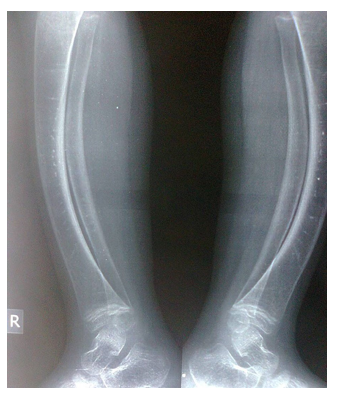

The younger sister laboratory tests performed during May, 2023 showed normal serum calcium of 9 mg/dL and normal serum phosphorus of 5.16 mg/dL. However, the alkaline phosphatase was high at 164 u/l (Normally less than 140 u/l). Old radiographs of the older sister showed osteopenia, fracture in the upper limb, and progressive bowing with no rachitic changes. Figure-2A and B shows a lower limb radiographs taken during December, 2019. Later radiographs showed more severe bowing (Figure-2C).

Old radiographs of the younger sister showed osteopenia, fracture in the upper limb, and progressive bowing with no rachitic changes. Figure-3A and 3B show lower limb radiographs showing progressive bowing. Figure-4 (A, B, C, and D) show recent bone radiographs of the younger sister taken during May, 2023 which showed osteopenia, bowing with no rachitic changes. Radiograph of the pelvis showed mild protrusio acetabula (Figure-4A). Radiograph of the wrist showed no rachitic changes (Figure-4B). Radiograph of the lower limbs showed bowing, cortical thinning with scanty spongiosa (Figure- 4C). Lateral skull radiographs showed platybasia (Figure-4D).

Figure-2A: A lower limb radiograph taken during December, 2019

Figure-2B: A lower limb radiograph taken during December, 2019

Figure-2C: Radiographs showed more severe bowing

Figure-3A: lower limb radiograph showing progressive bowing

Figure-3B: lower limb radiograph showing progressive bowing

Figure-4C: Radiograph of the lower limbs showing bowing, cortical thinning with scanty spongiosa